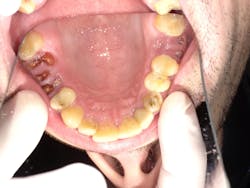

Maxillary arch occlusal view. Root tips are planned for extraction and implants for Nos. 3, 13, 14.

David paid cash and was on a limited income, so he chose to deal with the biggest problems first. We completed a comprehensive exam with x-rays and full probing. Rampant decay was noted as a result of drug use. Maxillary teeth Nos. 3, 13, and 14 all had had previous root canal therapies, but were decayed to the bone levels with only retained root tips present; no abscesses were present. Teeth Nos. 3, 13, and 14 all have hopeless prognoses and are planned for extraction, and implants will be done when the patient is ready. Nos. 8, 9, and10 were repaired at the initial visit as decay was close to the nerve space and causing pain. The images in this article were taken after anterior fillings were completed.